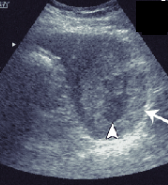

Identify this image.

Lymphoma